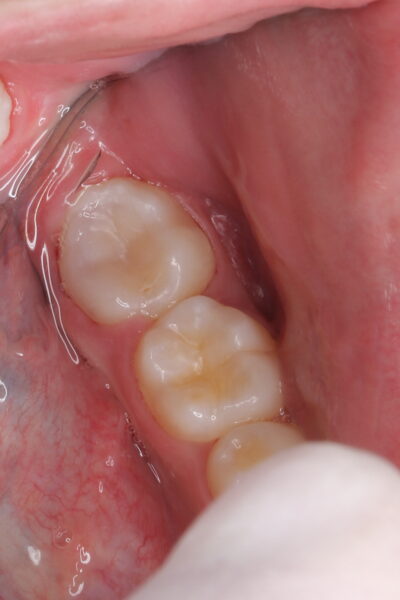

【術直後のレントゲンと口腔内写真】

ダイレクトボンディングにて修復し、異常なく安定しています。